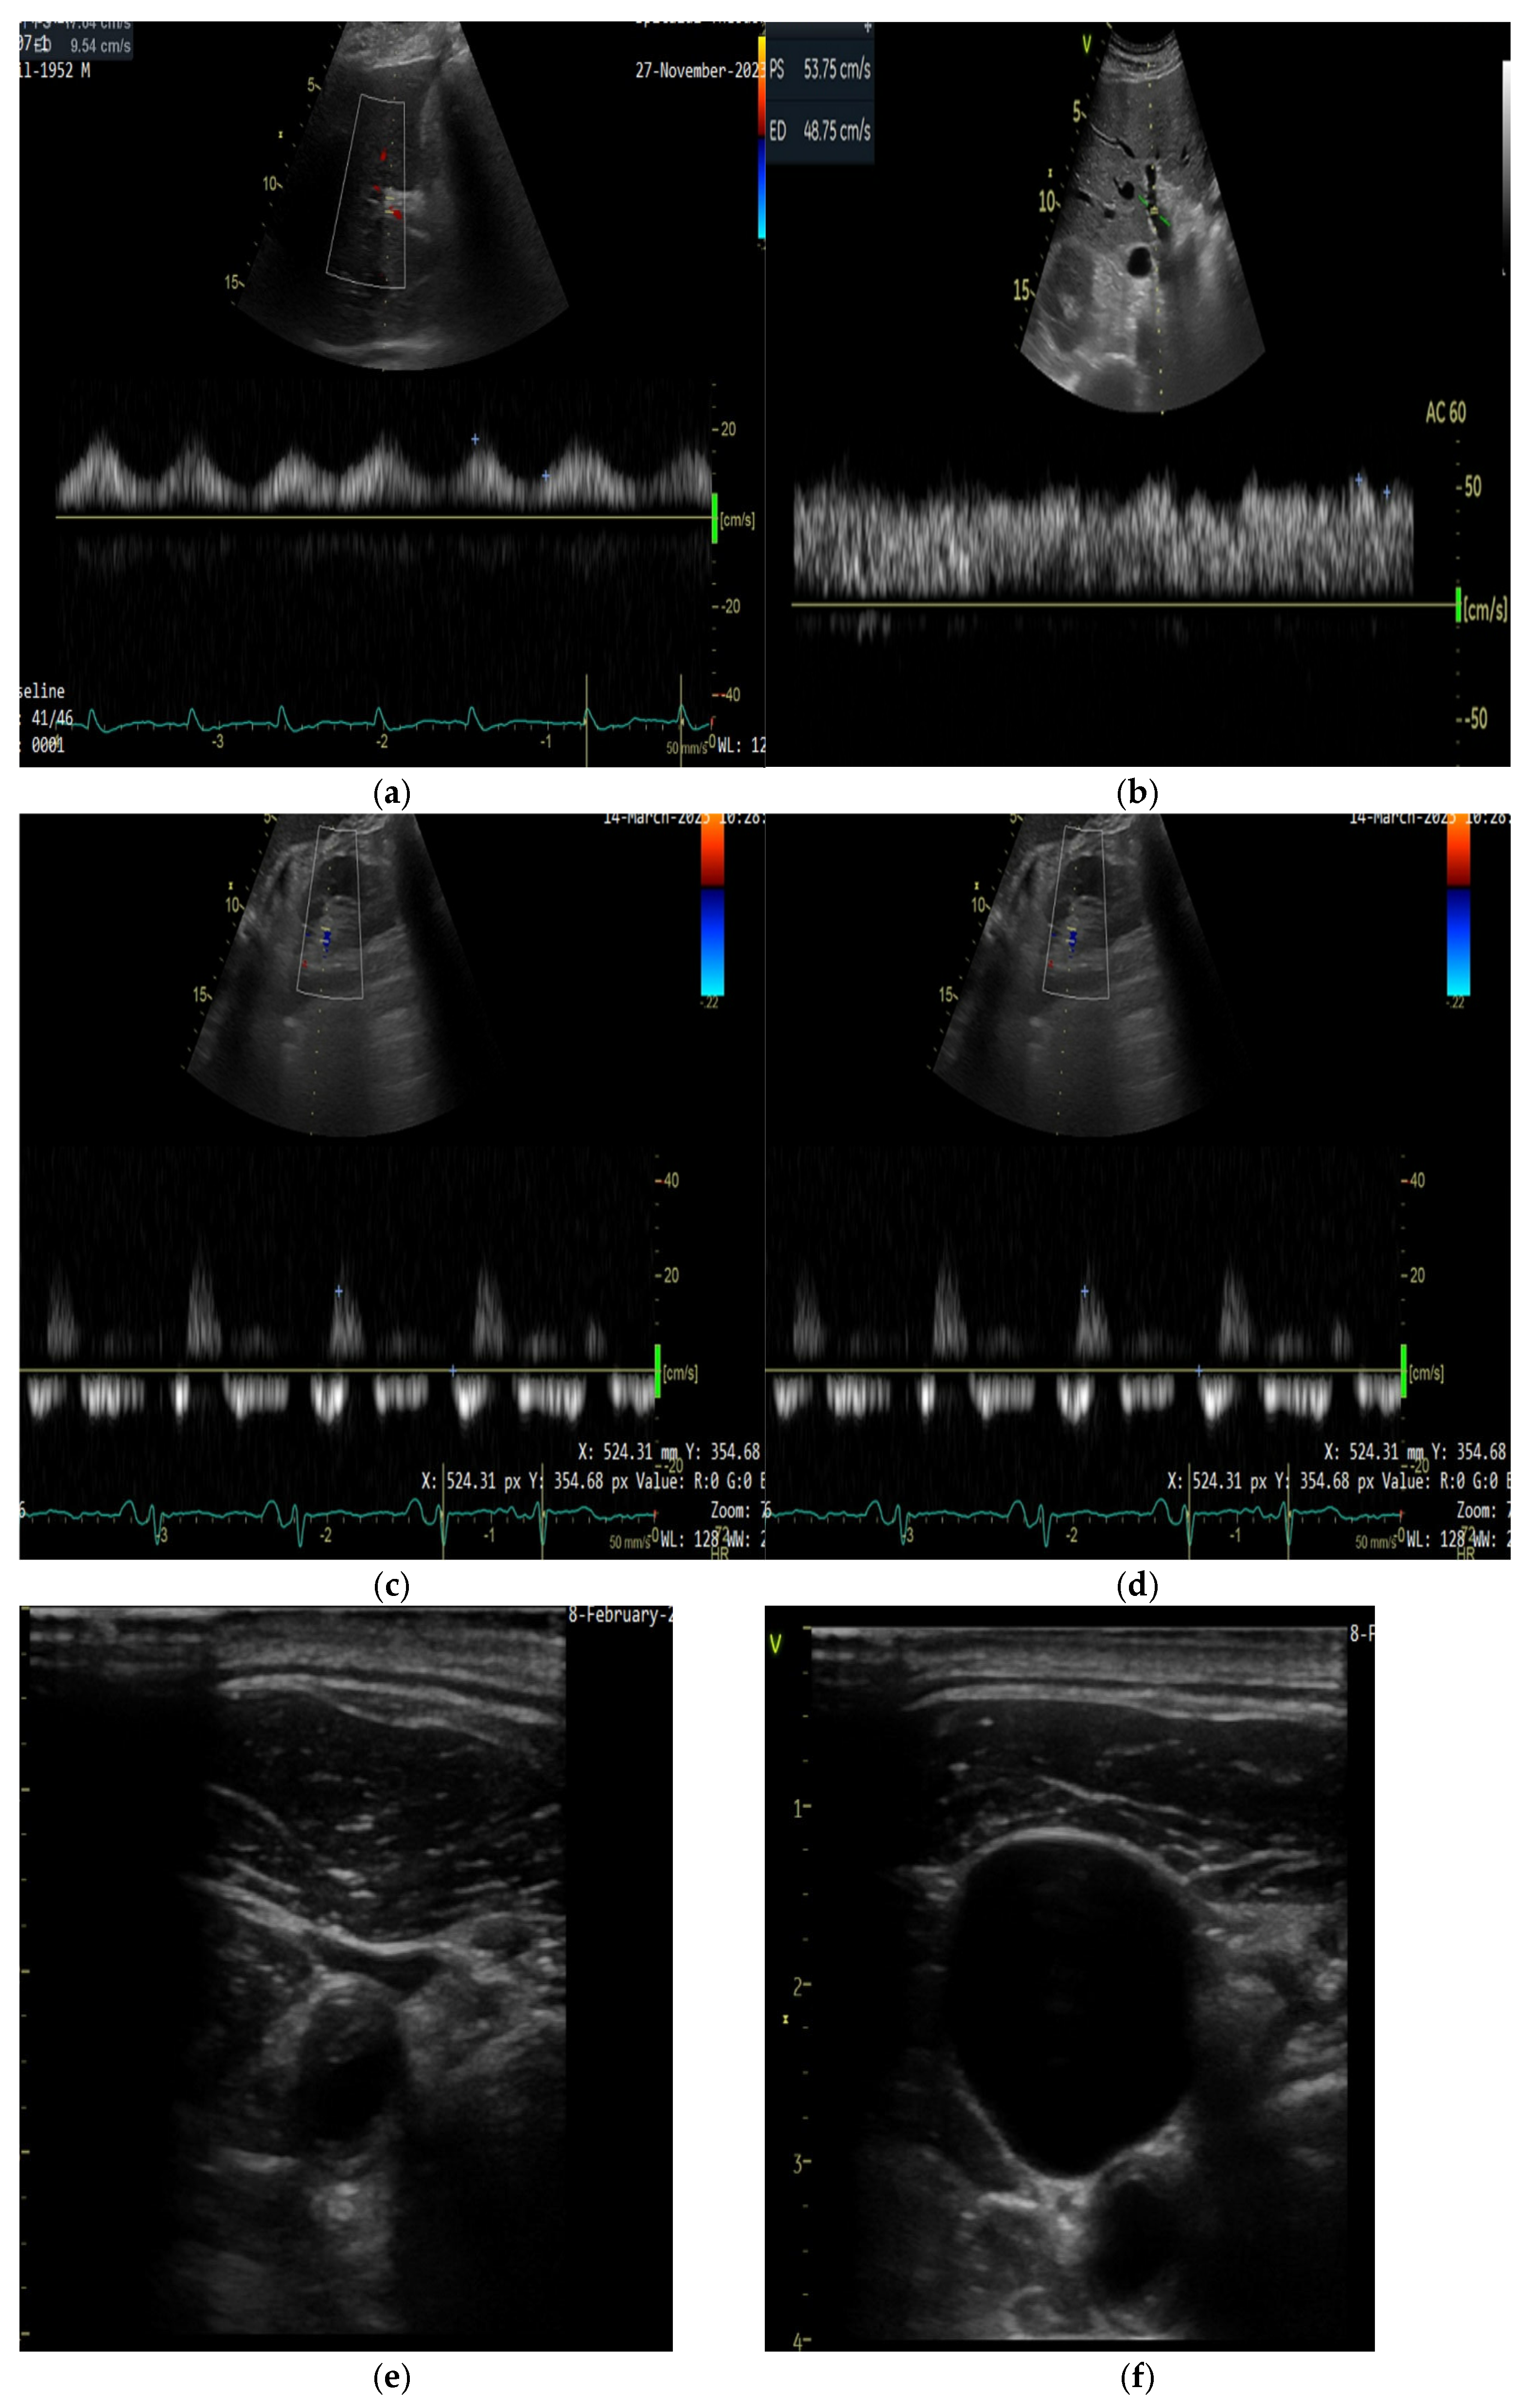

5.2.1. Ultrasound Assessment of Systemic Venous Congestion: Role of VExUS

5.2.2. Technical Aspects of Doppler Evaluation

- Grigore, M.; Grigore, A.-M.; Ilieșiu, A.-M. Portal Vein Pulsatility: A Valuable Approach for Monitoring Venous Congestion and Prognostic Evaluation in Acute Decompensated Heart Failure. Diagnostics 2024, 14, 2029. [Google Scholar] [CrossRef] [PubMed]